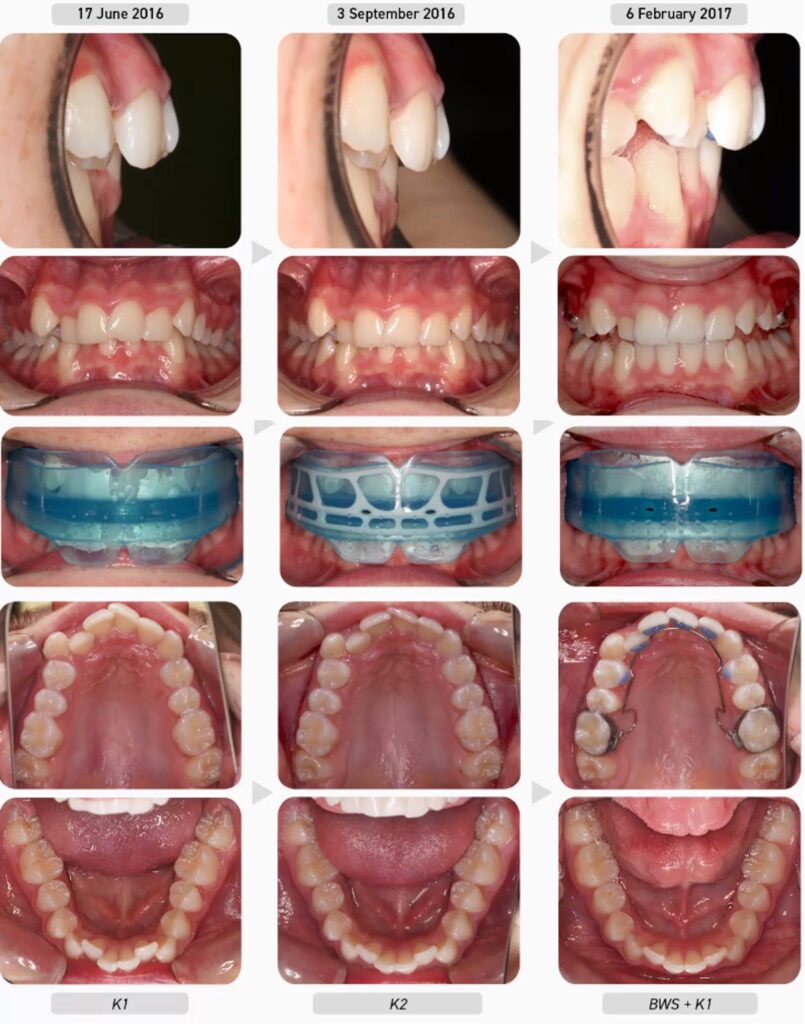

Ca lâm sàng 2

Bệnh nhân nữ 14 tuổi đến với than phiền chủ yếu là răng khấp khểnh. Bệnh nhân đang tìm kiếm ý kiến ​​​​thứ hai sau khi một bác sĩ chỉnh nha khuyên nên nhổ răng cối nhỏ và niềng răng. Vì mối quan tâm chính của bệnh nhân là răng nanh phía trên bên phải nhô ra sẽ bị lộ khi cười, nên muốn cải thiện độ thẳng hàng của răng cửa hàm trên mà không phải niềng răng. Sau khi được giới thiệu các lựa chọn điều trị khác nhau, quyết định thực hiện điều trị Myobrace đã được đưa ra, liên quan đến việc sử dụng loạt khí cụ Myobrace®, Hoạt động Myobrace® và, do mức độ nghiêm trọng của sai khớp cắn hiện tại, việc sử dụng khí cụ nới rộng BWS.

Trước điều trị:

Sử dụng biểu mẫu Đánh giá Chỉnh nha Cơ chức năng (MOE), ghi nhận bệnh nhân có hàm trên và hàm dưới kém phát triển với tình trạng chen chúc răng từ trung bình đến nặng. Cung răng trên rất hẹp và có hình đồng hồ cát. Cung hàm dưới cũng rất hẹp và phẳng với tất cả các răng sau nghiêng vào trong.

Ngoài ra còn cắn sâu và cắn chìa quá mức. Bệnh nhân ngủ ngáy và thói quen xấu bao gồm thở bằng miệng với tư thế lưỡi thấp và nuốt ngược nghiêm trọng. Vì đang trong giai đoạn răng vĩnh viễn nên thông thường bệnh nhân này sẽ được điều trị bằng loạt sản phẩm Myobrace® nhóm T. Tuy nhiên, bệnh nhân này thích khí cụ K1 (lớn) hơn khí cụ T1 do sự thoải mái, và do đó việc điều trị sẽ bắt đầu với dòng sản phẩm Myobrace® nhóm K (for Kid).

Tiến trình điều trị:

Bệnh nhân bắt đầu với khí cụ K1 để thiết lập thở bằng mũi và bắt đầu điều chỉnh các thói quen cơ chức năng. Ba tháng sau, chức năng hô hấp của bệnh nhân đã được cải thiện và do liên tục duy trì được K1 qua đêm nên được chuyển sang đeo khí cụ K2 (lớn) tập trung vào phát triển cung răng và tiếp tục điều chỉnh thói quen.